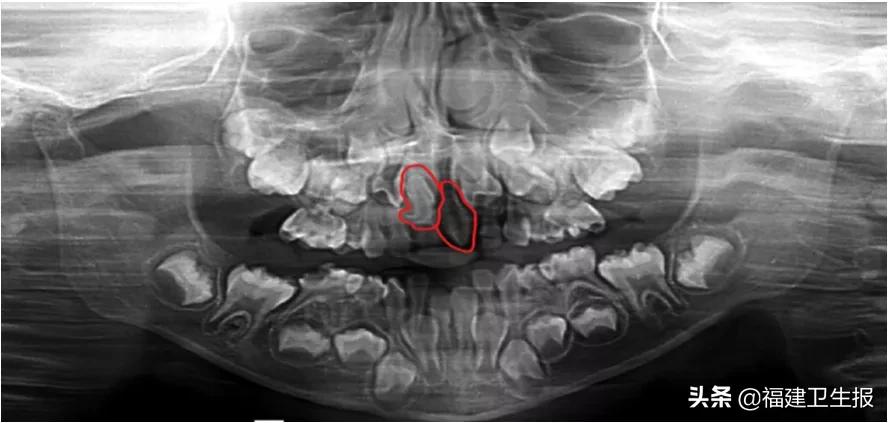

爸爸妈妈赶紧带着她去宁德市闽东医院就诊,口腔科陈艳主治医师接诊后,经过口腔拍片检查,发现悦悦上颌前牙区长了2颗牙,其中一颗还是倒置的。

超出正常牙列数目之外的牙齿被称为多生牙

主要集中于上颌前牙区

多生牙是一种常见的牙齿发育异常,可以是某些综合征的口腔表现,在临床上也可导致许多并发症,常会造成邻牙阻生、迟萌、异位或错位萌出、牙根吸收。